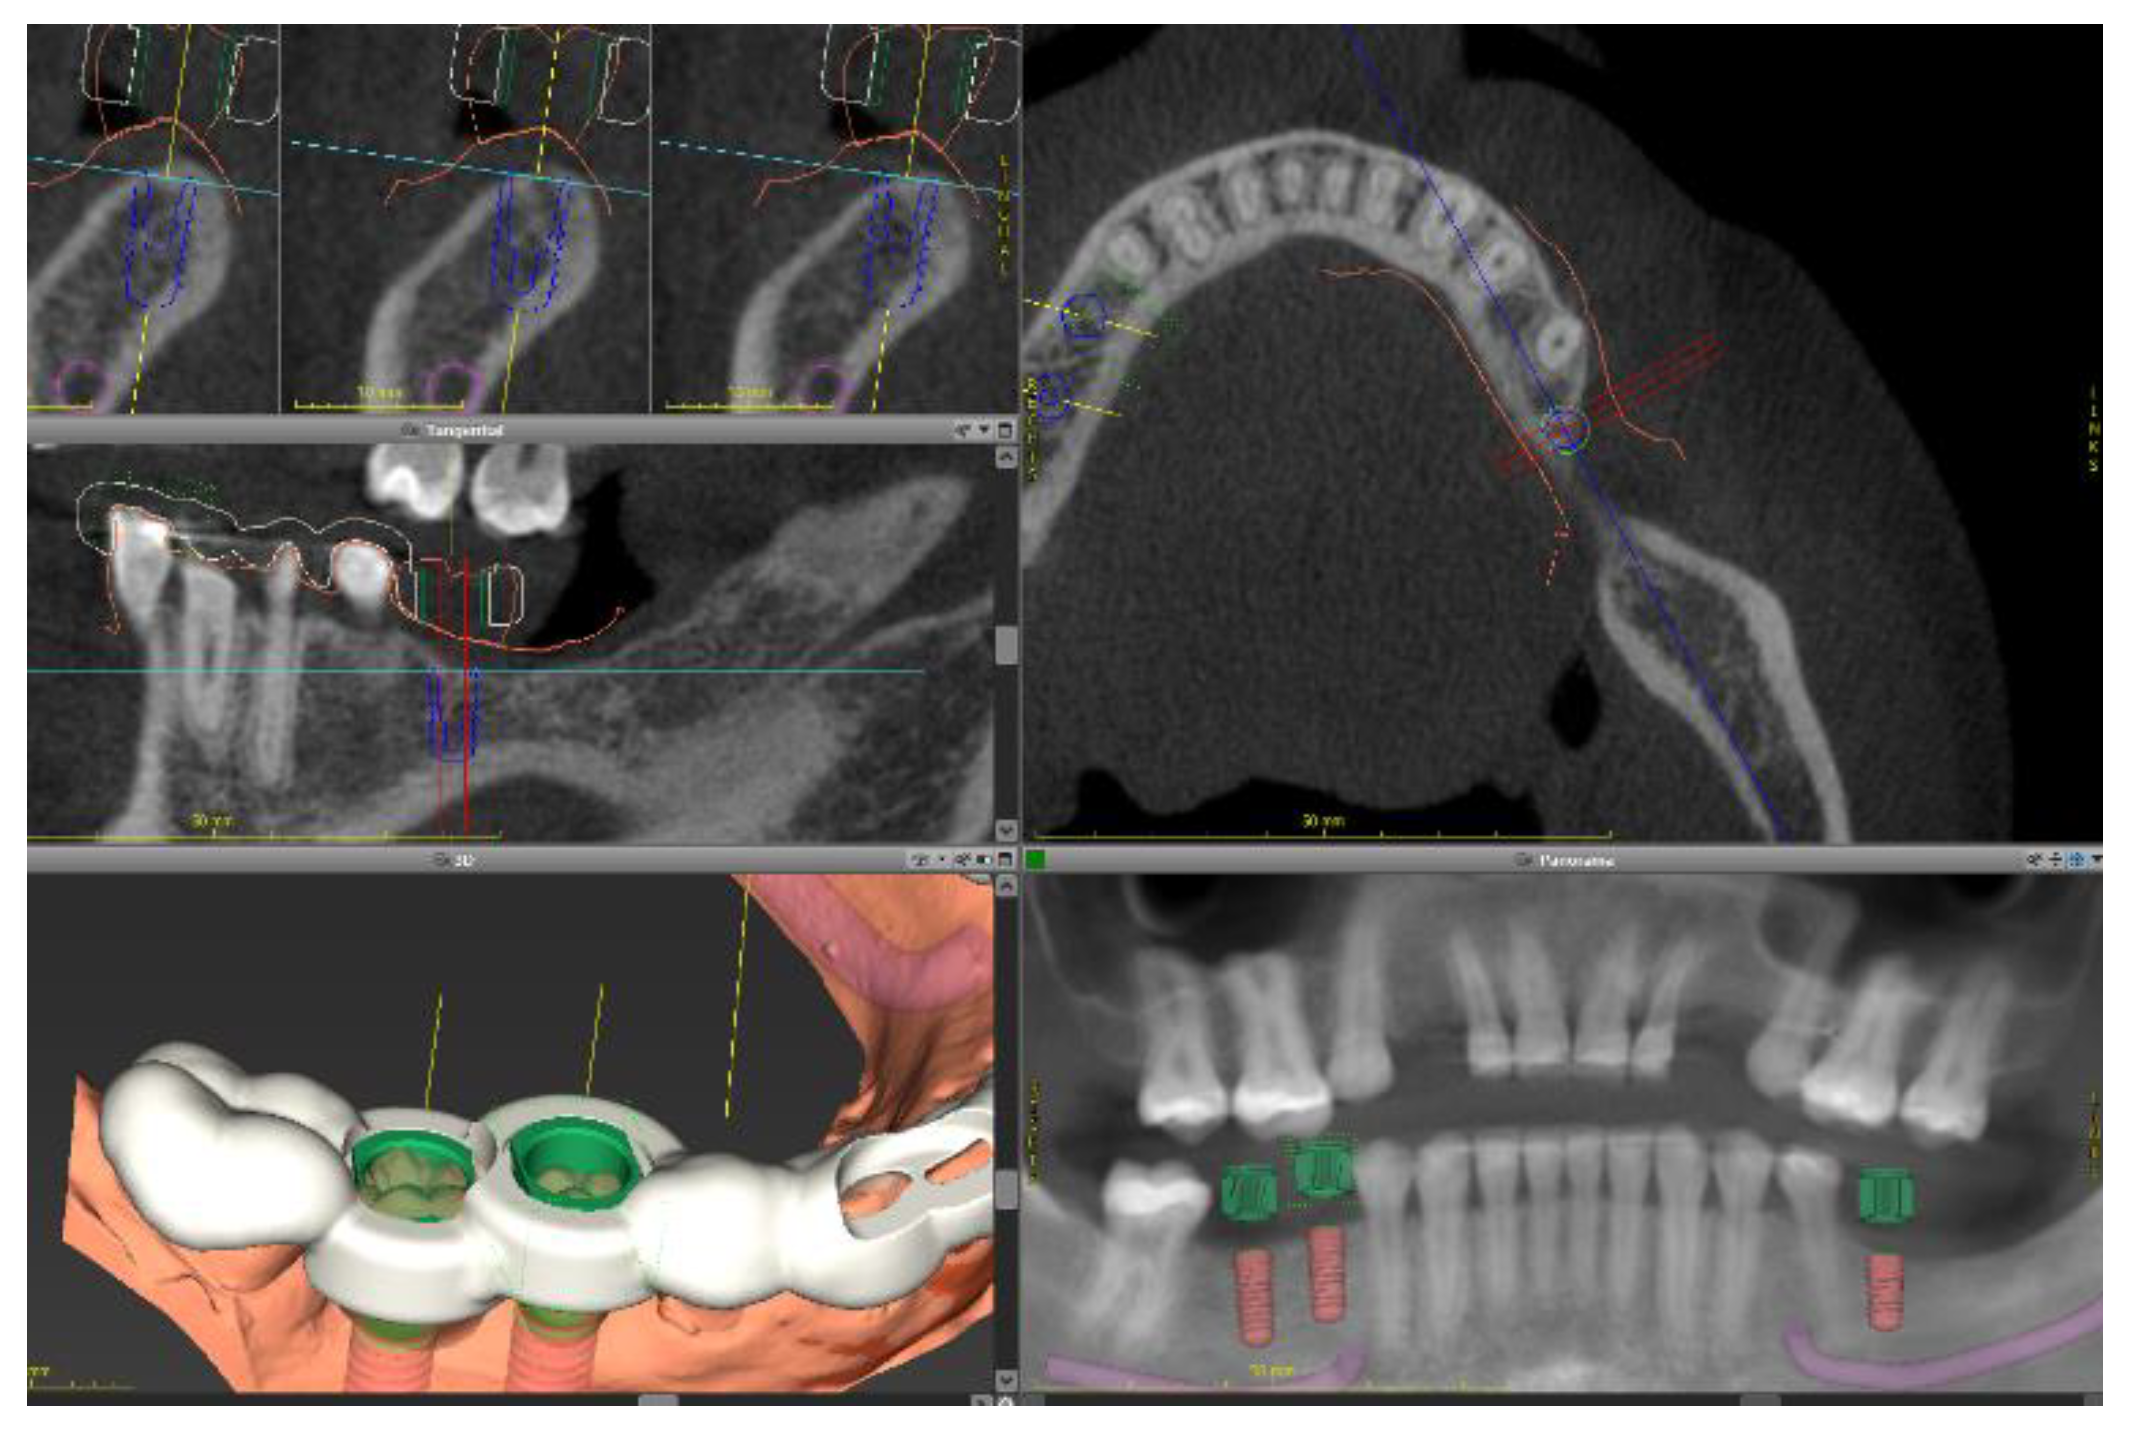

Figure 8.

Dental implant planning on lower jaw. Sagittal cuts of cone-beam computed tomography (DICOM files) are shown (a). DICOM files were superimposed to the intraoral casts (b) and to the digital wax-up (c) to determine the optimal implant position.

Due to aesthetic concerns, the surgical procedure was planned digitally. CBCT imaging of both jaws was acquired with a CBCT device (Kavo). The examination showed sufficient bone volume on edentulous spaces. Thus, no bone or soft tissue graft procedures were required. A dental impression was taken with alginate and scanned with a desktop scanner (3Shape). In addition, a wax-up was designed digitally. Dental implant planning was conducted with the software Co-DiagnostiX, as described above (Figure 8). The CBCT images were matched to the intraoral digital casts and to the digital wax-up. On the basis of the implant planning, a surgical guide was designed and printed (Figure 9).

Figure 9.

Design of a surgical guide to be used as a reference to dental implant placement.